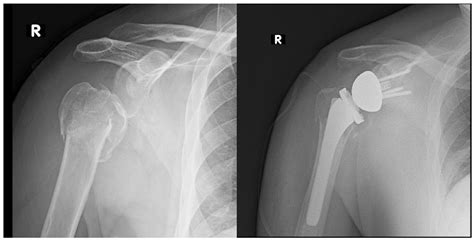

To understand why this procedure is so effective, it is helpful to first visualize the anatomy of a healthy shoulder. In a natural shoulder, the head of the humerus (the upper arm bone) acts as a ball, while the glenoid (the shoulder socket) acts as a socket. In Reverse Shoulder Surgery, the surgeons essentially flip this structure: they attach a metal ball to the shoulder socket and fix a plastic cup to the top of the humerus. By reversing the anatomy, the procedure relies on the powerful deltoid muscle rather than the damaged rotator cuff to lift the arm. This shift is what makes it a game-changer for patients who have lost the functional integrity of their rotator cuff muscles.

The surgery itself typically takes several hours and is performed under general or regional anesthesia. During the procedure, the surgeon carefully removes the damaged surfaces of the joint and prepares the bone to accept the prosthetic components. Once the new "reverse" joint is securely in place, the incision is closed, and the arm is placed in a sling to initiate the protection phase of healing.